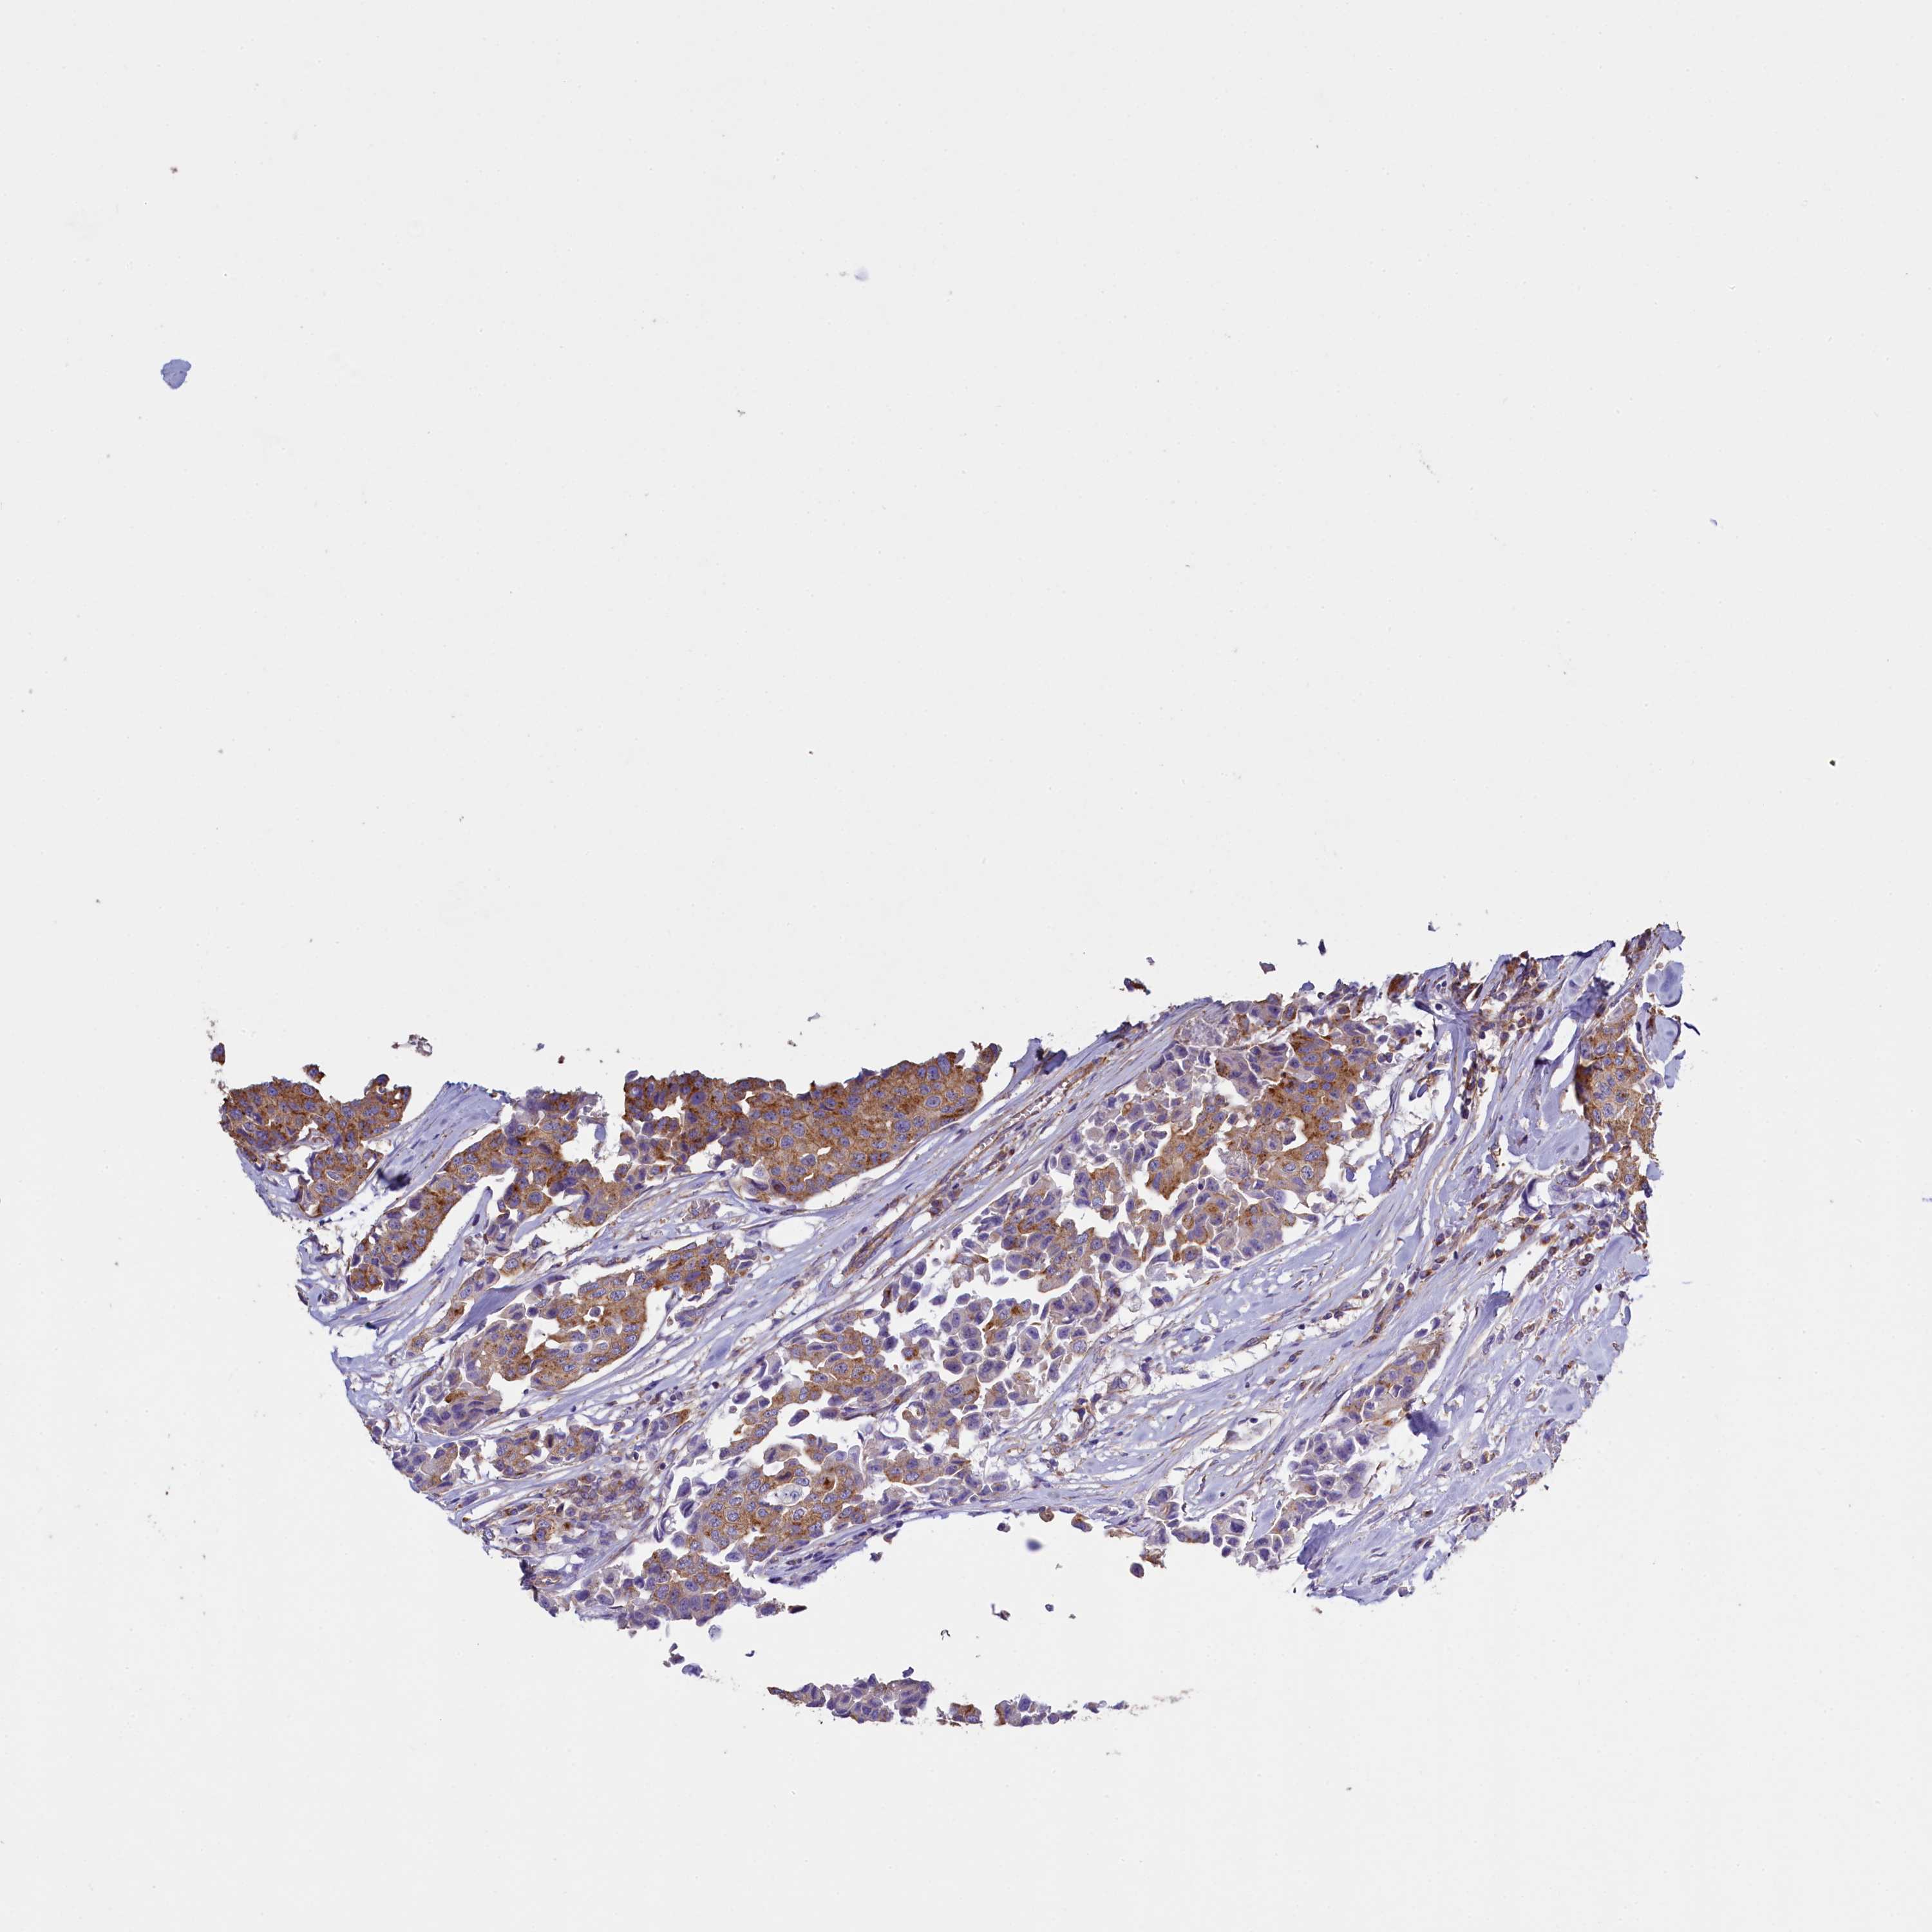

CANCER BREAST CANCER Show tissue menu

BRCA TCGA BRCA VALIDATION PROTEIN EXPRESSION